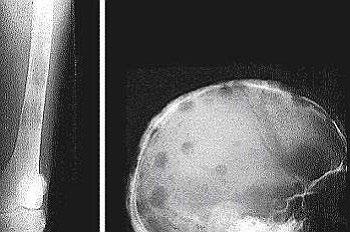

Myeloma Bone Disease

Myeloma in hand

Myeloma in the orbit

MRI (with contrast or STR images) very useful to delineate problems

MRI and FDG-PET in Multiple Myeloma

• > 3 focal lesions or SUV > 4.2 at diagnosis results in shorter PFS and OS[1]

• 65% of pts PET/CT negative 3 mos after ASCT with longer PFS and OS vs PET positive[1]

• Complete FDG suppression associated with durable disease control and prolonged OS[1]

• Skeletal survey recommended in cases of plasmacytoma, extramedullary disease, suspected spinal cord compression as well as with new symptoms or progression[2]

• MRI and/or PET/CT indicated when symptomatic areas show no abnormality on radiograph[3]

1. Zamagni E, et al. Blood. 2011;118:5989-5995. 2. Ludwig H, et al. Leukemia. 2014;28:981-992. 3. NCCN. Clinical practice guidelines in oncology: multiple myeloma. v.2.2014. 4. Boot M, et al. Novel prognostic modalities in multiple myeloma. 2013. MRI FDG PET Imaging Techniques[4]